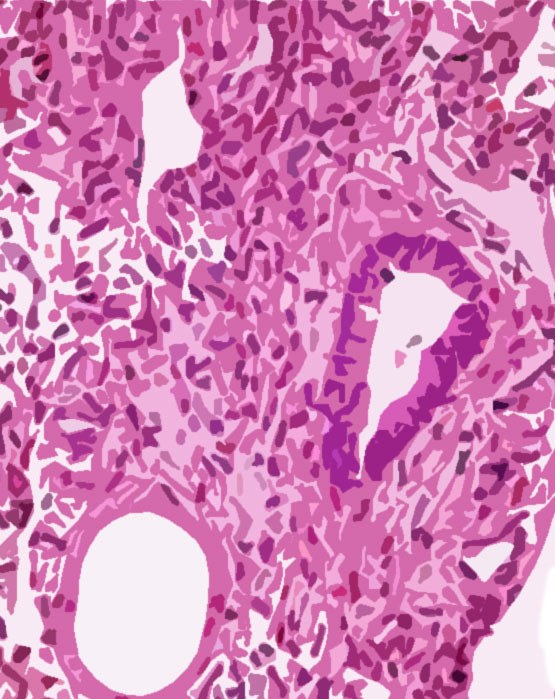

Για επιστημονικά ανεπιβεβαίωτους μέχρι στιγμής λόγους, κατά τη διάρκεια της κύησης, η μήτρα του εμβρύου μπορεί να πάρει σχήμα ταυ. Αυτή η όχι και τόσο σπάνια δυσπλασία της μήτρας, ενίοτε, συνδέεται ιατρικά με την υπογονιμότητα (σ. 47)